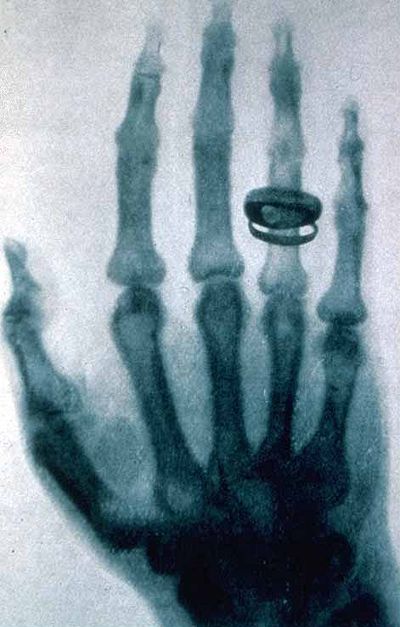

Бир жолу Рентген өзүнүн изилдөөсүн жеңилдетүү үчүн бөлмөнү караңгылатып туруп Крукс түтүкчөсүн кара барак менен бекем ороп салган. Ошондо ал экрандан анча алыс эмес жерде цианоплатин барийи менен капталган жарыктын таасири менен өзүнөн жарык чыккан сызыкчаларды көргөн. Ошондон кийин ал өзүнүн изилдөөсүн жети жума бою токтоосуз жүргүзүп, акырында разряддык түтүкчө менен экрандын ортосунда өтө чоң эмес коргошун дискти кармап турганда икс-нурунан Рентгендин колунун манжаларынын сөөктөрү экрандан көрүнүп калган. Ошентип Рентген дүйнөдө биринчи болуп рентген аппаратын ойлоп тапкан. Анын икс-нурун окумуштуулар "рентген нурлары" деп атап калышкан. Рентген өзүнүн изилдөөсүн тастыктоо үчүн аялынын манжаларын рентгенден өткөрүп, даана-так түшүп калган колдорунун фотосүрөттөрүн таркаткан. Анын изилдөөсү тууралуу биринчи жолу 1895-жылы жергиликтүү илимий журналга жарыяланып, ал илимий чөйрөгө жана коомчулукка чоң кызыкчылык туудурган жана анын изилдөөсүн илимпоздор дароо эле тастыкташкан.1913-жылы медицинада рентген ыкмасы өзүнүн туруктуу ордун тапкан. Мындай жетишкендиги аркылуу Рентген 20-кылымдын башында физика тармагында революция жасоо менен бирге медицина тармагында да чоң ачылыш жасаган.